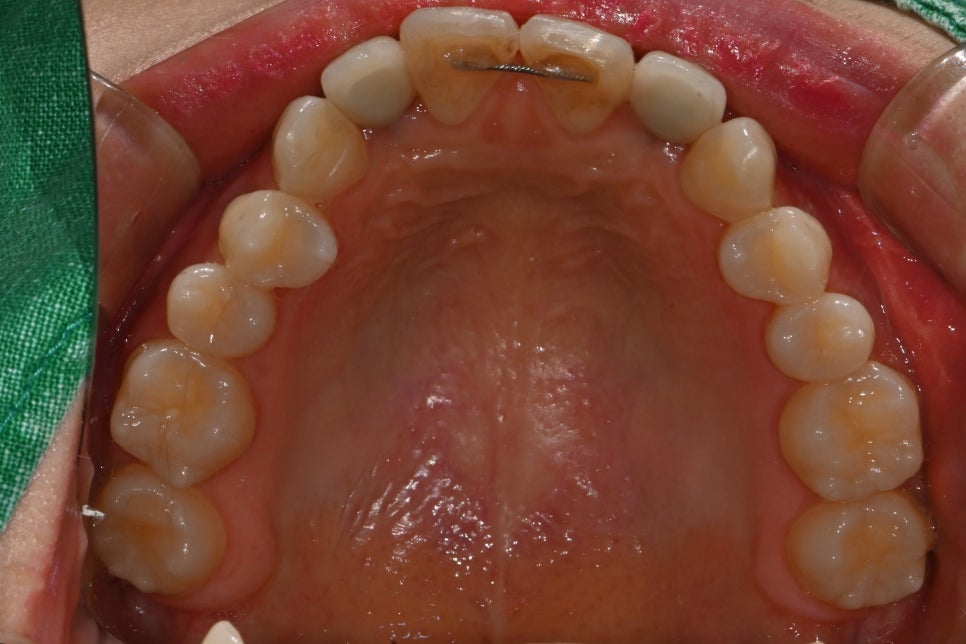

실제로 앞니 심미치료에서는 단순히 치아 색만 맞춘다고 자연스러워지는 것이 아니라, 치아의 폭경, 길이, 라인, 표면 질감, 잇몸과의 조화, 좌우 대칭감까지 함께 고려해야 만족도 높은 결과가 나옵니다.

치료 계획

이번 케이스에서는 환자분의 기존 치아와 임플란트 상태를 면밀히 확인한 뒤, 전체적인 심미 밸런스를 맞추기 위해 다음과 같은 방향으로 치료를 계획했습니다.

저희 서울오브치과는 라미네이트 진료가 가능한 치아보철과, 구강악안면외과 전문의가 직접 진료하기 때문에 두 가지의 시술을 문제 없이 진행할 수 있습니다.